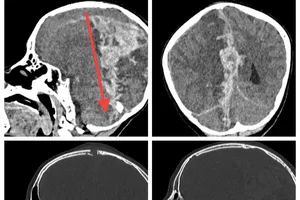

Bé gái 6 tuổi bị thân vợt cầu lông xuyên vào đầu